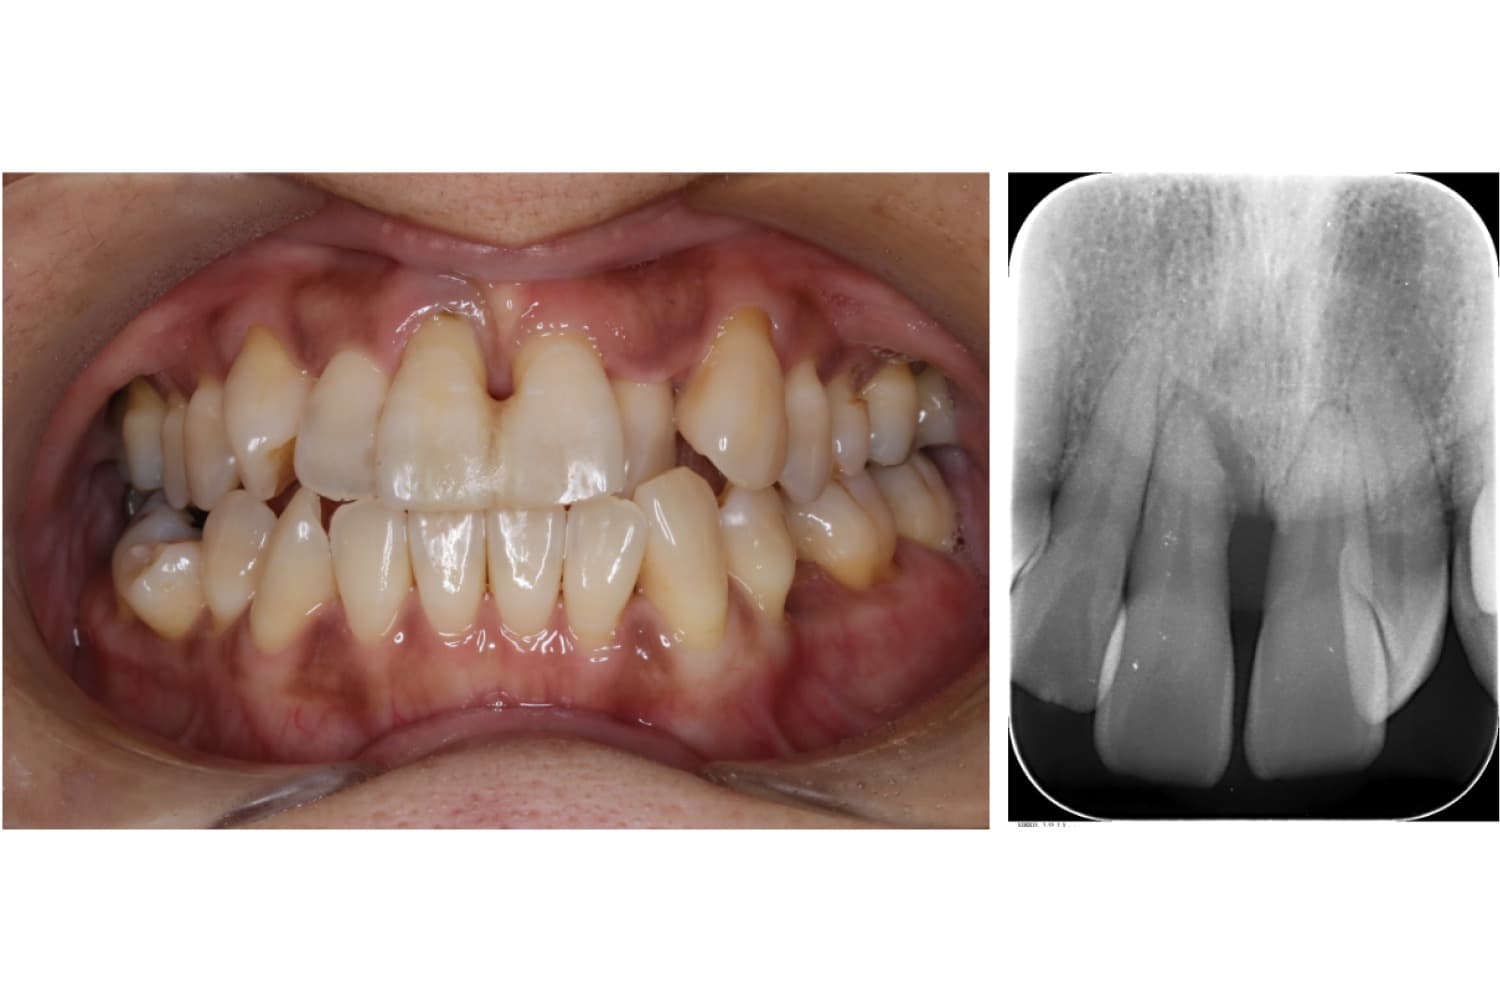

右上前歯のインプラント治療

Before

After

右上前歯の部位に失った骨を造る処置(GBR、骨造成)と同時にインプラント治療

年齢

40代

性別

女性

主訴

前歯がぐらついて噛むことができない

治療期間

9ヵ月

治療回数

9回

費用

CT 16,500円(税込) インプラント治療 525,800円(税込) 造骨処置 88,000円(税込)

副作用・リスク

歯周病に感染・発症し重度に進行するとインプラントが抜けてしまうことがあります。また、手術後は数日間腫れが出る場合があります。造骨処置をおこなった部分に内出血などがあらわれる場合があります。